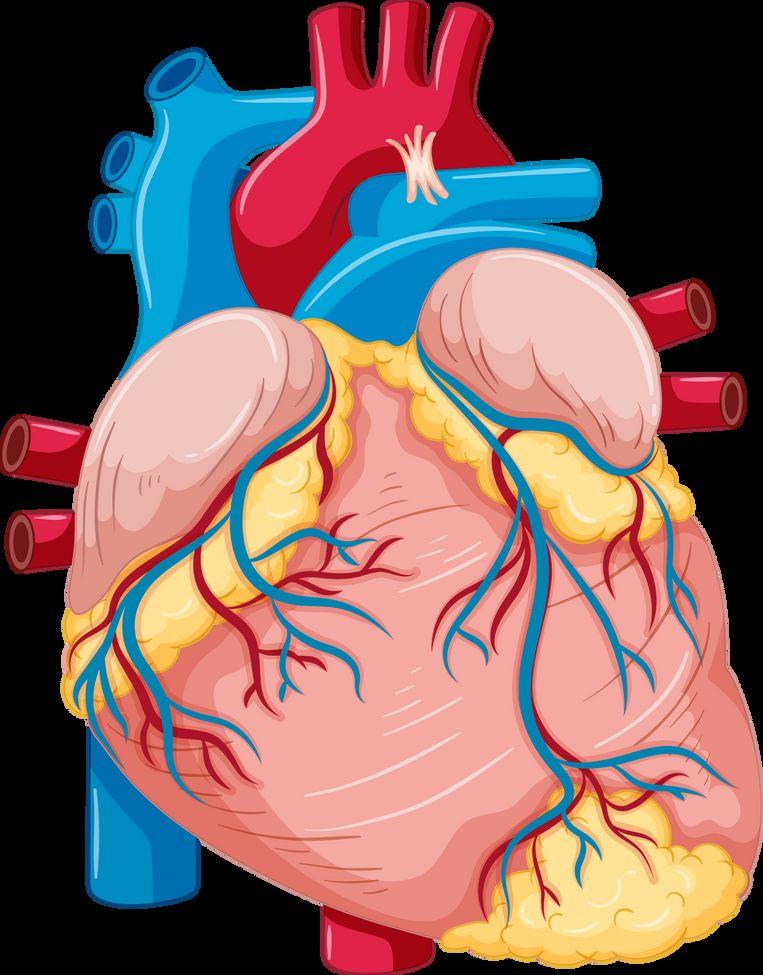

The oral-systemic link

Heart disease Strokes